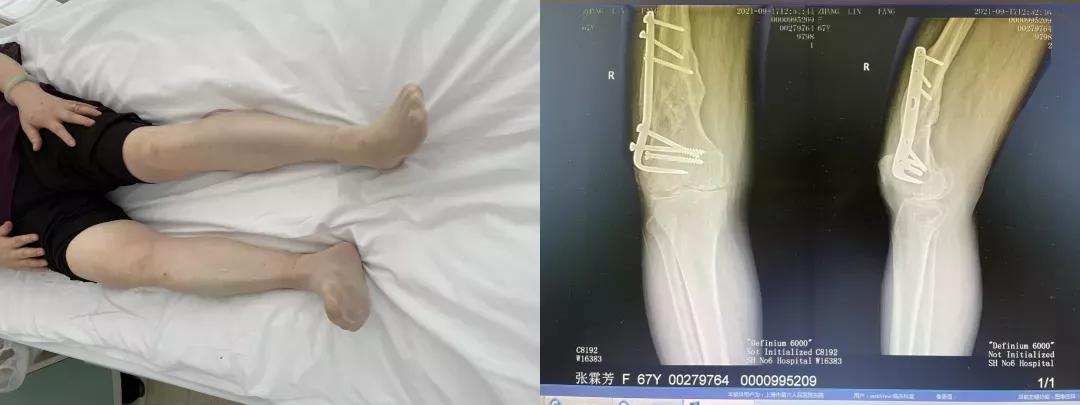

67岁的张女士,在6年出现右膝关节疼痛,自行服用止痛药缓解症状。近2年来症状加重,出现持续性的中到重度疼痛,行走时症状加重,同时伴有膝关节屈曲受限。药物等保守治疗无效,为求进一步诊治,张女士来到上海市第六人民骨科求诊,门诊摄片提示右膝关节退行性骨性关节炎,予以收治入院。

(手术前)

在经过充分的术前准备后,刘万军主任团队为张女士进行了计算机导航辅助下的全膝关节置换+膝关节清理+髌骨成形术。术中行内松解后见髌骨、股骨、胫骨软骨广泛磨损破坏,骨赘增生。予以清理关节腔,切除半月板和增生骨赘,行髌骨修整。股骨根据髓外力线定位并截骨,仔细做软组织松解后,评估软组织平衡,试装假体复位,调整垫片松紧度,骨水泥固定安装假体和胫骨垫片。手术进行地较为顺利,术中出血较少。

(手术后)